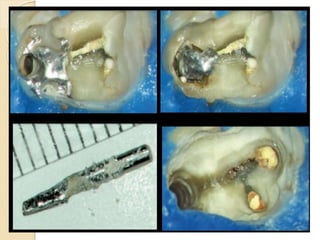

(A) Intermediary magnification of endodontic access on tooth No. 15 (note there is

no sign of canals). (B) Dentin smear resulted from ultrasonic instrumentation of

pulp

floor. (C) Groove produced after ultrasonic usage. (D) Mesiobuccal (MB) and

second MB

(A) Intermediary magnificationof endodontic access on tooth No. 15 (note there is no sign of canals). (B) Dentin smear resulted from ultrasonic instrumentation of pulp floor. (C) Groove produced after ultrasonic usage. (D) Mesiobuccal (MB) and second MB